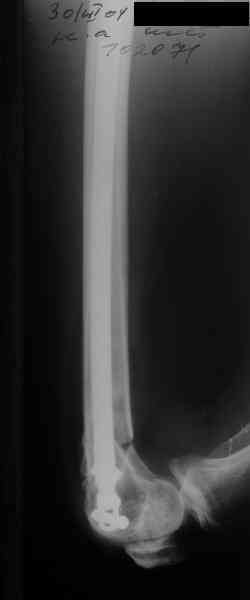

А в чем проблемы? Пример в приложении.

Насчет снимка Вами представленного - смотрится оч красиво, еще бы на функцию узнать...

В приложении функциональные снимки в 3 мес. и в 1 год.